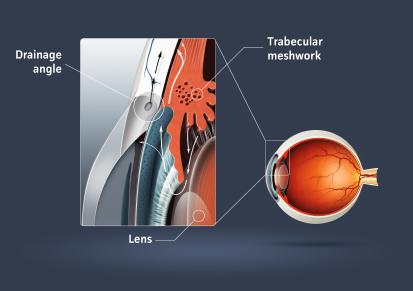

Η ενδοφθάλμια πίεση δημιουργείται από το υγρό που γεμίζει το πρόσθιο τμήμα του ματιού και ονομάζεται υδατοειδές υγρό. Αυτό το υγρό παράγεται πίσω από την ίριδα σε μια περιοχή που ονομάζεται ακτινωτό σώμα. Το υγρό αυτό δια μέσω της κόρης έρχεται εμπρός από την ίριδα και κινείται προς την περιοχή που σχηματίζεται από τον κερατοειδή (το διαφανές παράθυρο του ματιού) και την ίριδα ,την γωνία του ματιού, απ’ όπου και αποχετεύεται. Στα φυσιολογικά μάτια υπάρχει ισορροπία μεταξύ του παραγόμενου και του αποχετευόμενου υγρού. Όταν αυτή η ισορροπία διαταράσσεται, λόγω συνήθως μείωσης της αποχέτευσης, τότε αυξάνεται η πίεση στα μάτια.

Πρωτοπαθές γλαύκωμα ανοιχτής γωνίας, πρωτοπαθές γλαύκωμα κλειστής γωνίας, δευτεροπαθές γλαύκωμα και συγγενές γλαύκωμα.

Πρωτοπαθές Γλαύκωμα ανοιχτής γωνίας

Αυτός ο τύπος γλαυκώματος είναι συχνότερος στους ασιάτες. Η ενδοφθάλμια πίεση αυξάνει ξαφνικά (οξύ γλαύκωμα) και προκαλεί έντονο πόνο στην περιοχή του ματιού που συνοδεύεται από έγχρωμους κύκλους γύρω από τα φώτα, θάμπωμα στην όραση και κόκκινο μάτι. Είναι επείγουσα κατάσταση που απαιτεί άμεση αντιμετώπιση.